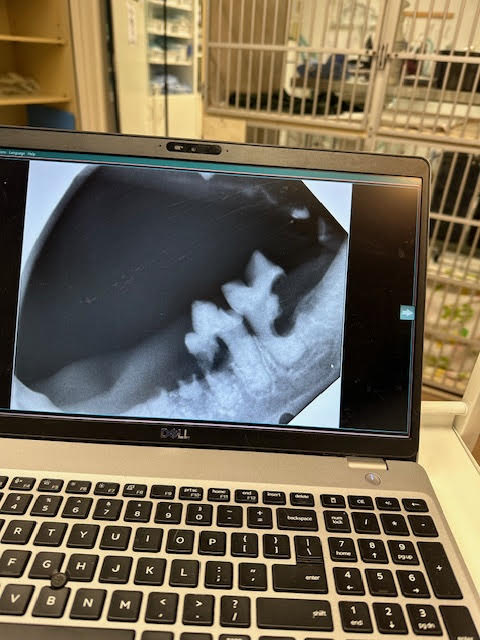

Comprehensive Full Mouth Digital Dental X-Rays

At our veterinary clinic, we take pride in offering comprehensive full mouth digital dental x-rays as part of our dental cleaning, scaling, and polishing services. These advanced x-rays allow our experienced veterinarians to see beyond the visible surface and delve below the gumline. Here's why they matter:

1. Early Detection of Pathology:

• Our digital x-rays reveal hidden dental issues that may not be apparent during a routine examination.

• We can identify dental diseases such as periodontal disease, tooth resorption, and abscesses.

2. Precision and Accuracy:

• Digital technology provides high-resolution images, allowing us to assess teeth, roots, and surrounding structures with exceptional clarity.

• This precision helps us make informed decisions about treatment options.

3. Surgical Planning:

• When pathology is detected, our veterinarians can plan surgical extractions if necessary.

• Diseased teeth can cause pain, discomfort, and even systemic health problems. Removing them improves the overall well-being of your pet.